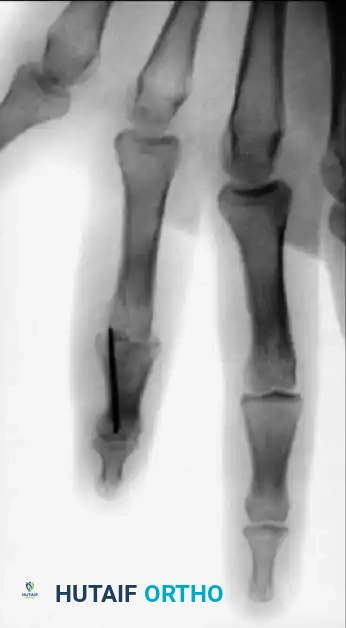

Malunion of a metacarpal shaft or of a phalanx can also be treated with a medullary cortical bone peg; however, the peg must be shaped meticulously to fit snugly without causing iatrogenic comminution.

Fig. 64-72 Malunion of a metacarpal shaft treated with a medullary cortical bone peg.